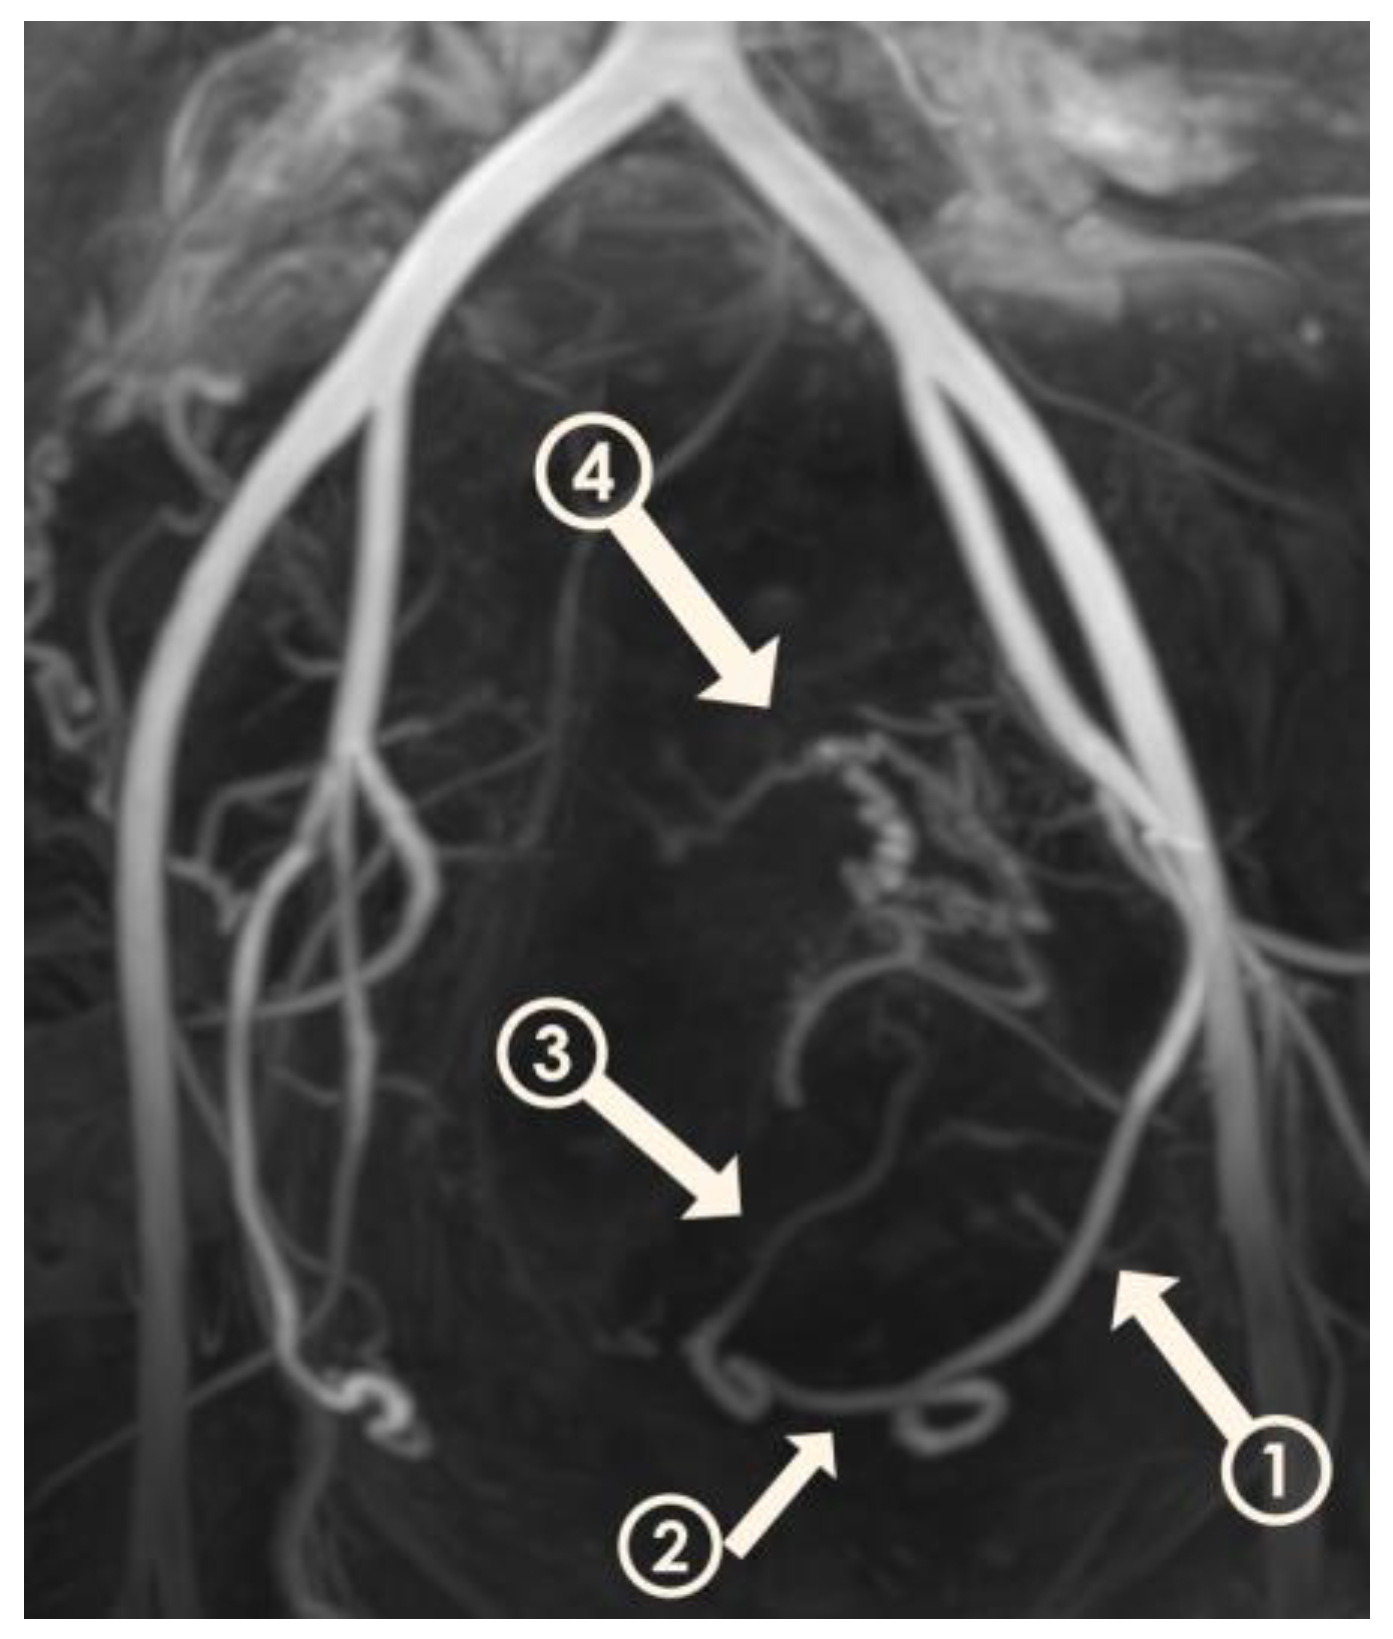

Figure 2.

Three-dimensional non-contrast-enhanced magnetic resonance angiography image from a 49-year-old woman. The model is rotated to show the left uterine artery and its segments. Descending segment (arrow 1); transverse segment (arrow 2); ascending segment (arrow 3); peritumoral plexus (arrow 4).